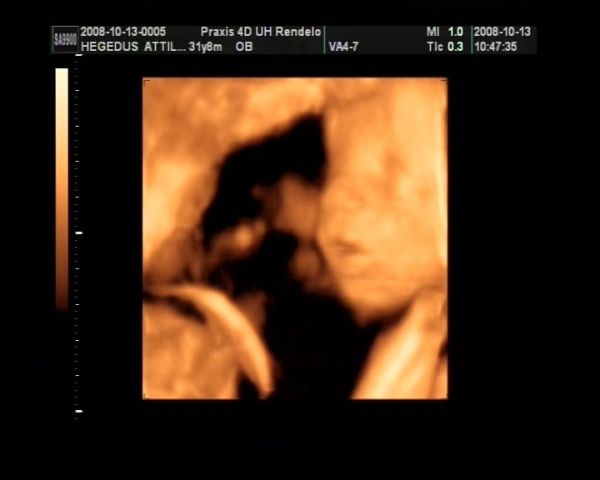

Tegnap voltunk 4d-s uh-on :) Hatalmas élmény volt. Viszont lesz egy komoly beszélgetésem a kisfiammal :) El kell magyaráznom neki, hogy a lányokra még nézni is csak szépen szabad, homlokon rugdosni őket pedig abszolút tilos. Még nézni is fájt, hogy miket művelt Eszterrel... Konkrétan az arcába ült, vagy a combját nyomta a nyakához, egyszer meg sarokkal homlokon rúgta. Mekkora harcok mehetnek bent... Eszterkém pofijáról nem is készült sok jó kép, mindegyiken belelóg Ádám feneke. Egyébként csodaszép két kölök, és makkegészségesek. Most épp fejjel lefelé voltak mindketten, de ahogy elnéztem őket ez egyelőre még kb 10 percenként változik :) És akkor a képek:

Ádámbátyám:

Kép

És Eszter: